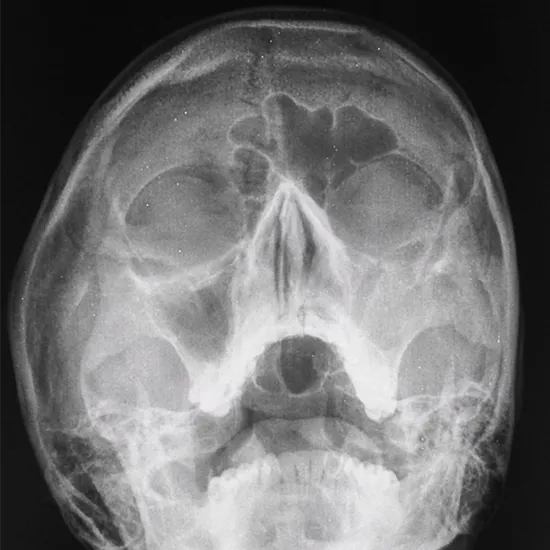

The most prominent sinuses are the maxillary sinuses. They are near your upper jaws, or maxillae, behind your cheekbones. Previously, an X-ray of the sinuses was the gold standard for detecting whether a person had acute sinusitis in the sinuses situated behind the cheeks (maxillary sinuses).

Abnormal sinus X-ray results may indicate the presence of sinus fluid or a thicker mucous membrane. This strongly suggests a sinus infection.

An X-ray of the sinuses may also be used to identify other sinus issues, such as a tumor or bleeding in the sinuses.